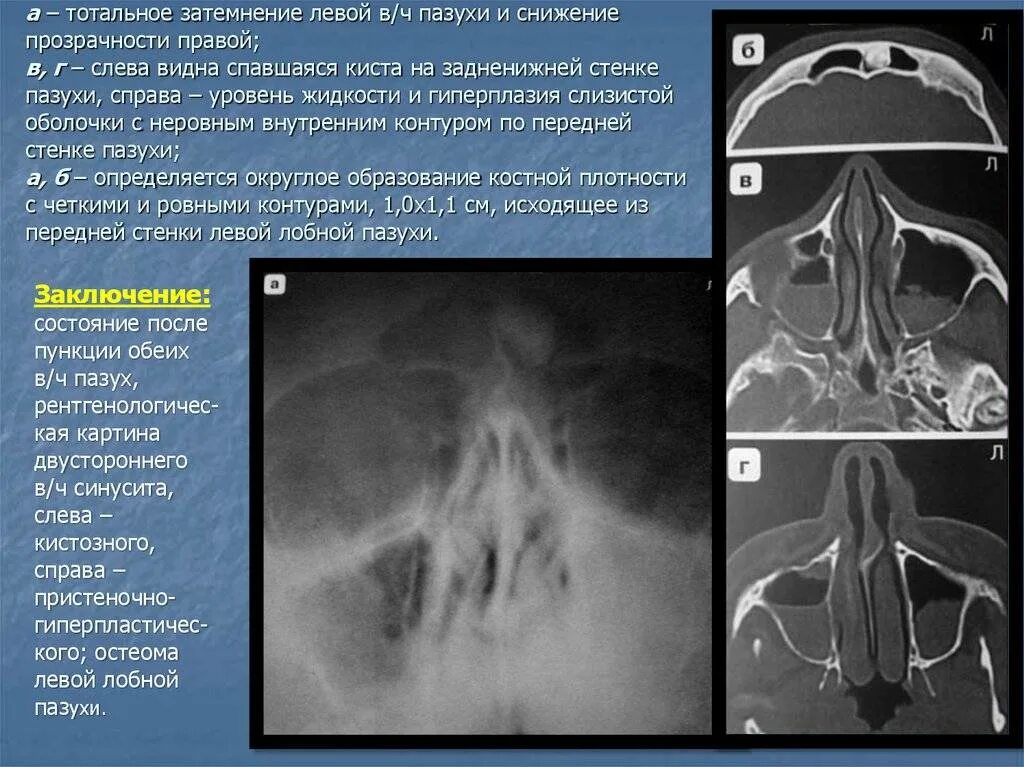

Утолщение верхнечелюстной пазухи что это значит